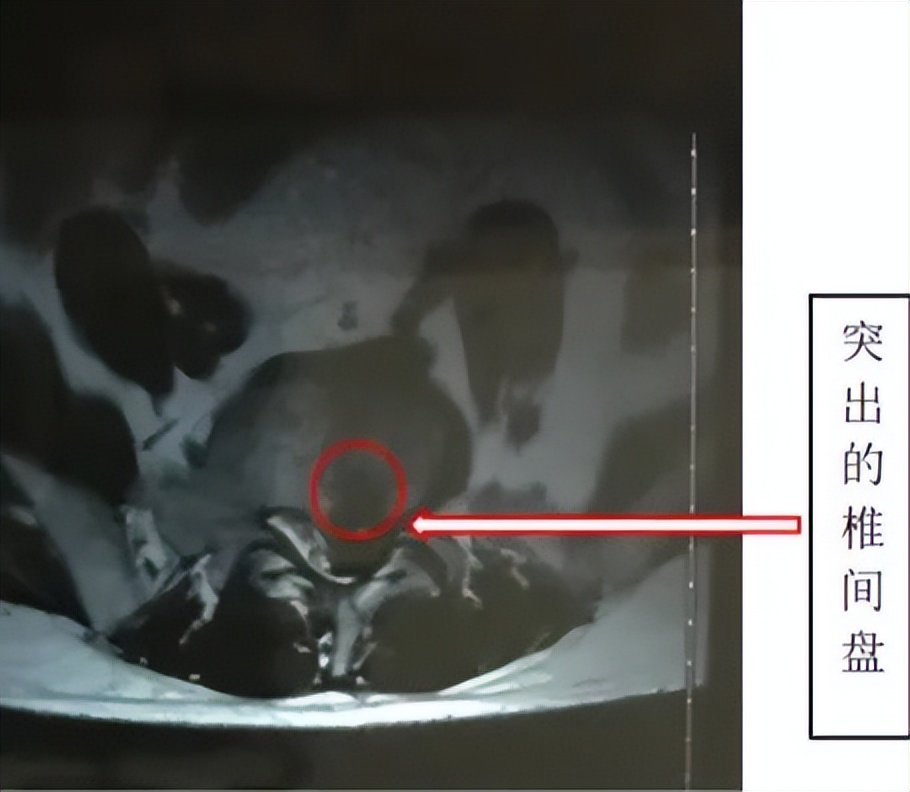

腰椎间盘突出症”是在腰椎间盘突出的病理基础上,由突出的椎间盘组织刺激和(或)压迫神经根、马尾神经所导致的临床综合征,表现为腰痛、下肢放射痛、下肢麻木、下肢无力、大小便功能障碍等。

多见于青壮年,好发于20岁~40岁之间,男性多于女性,以L4/L5和L5/S1椎间盘病变发生率最高。